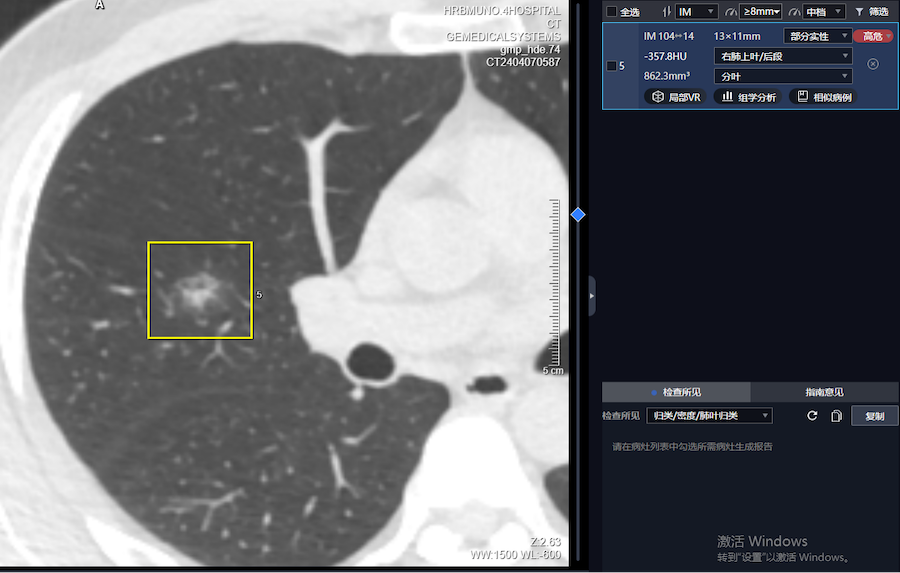

image.png

图二:实性结节